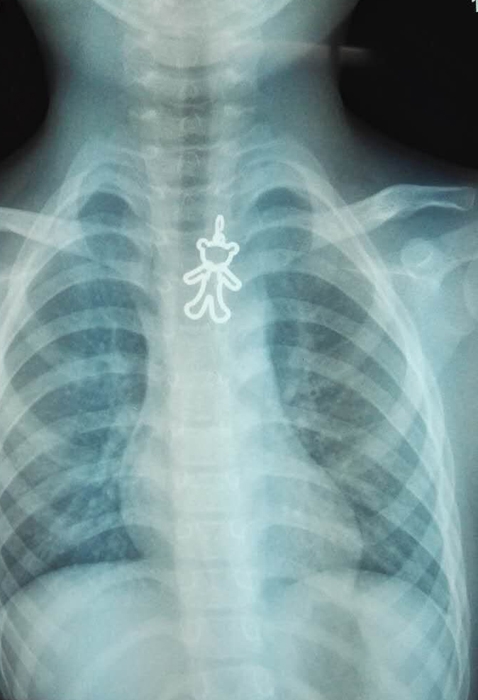

??? 緊急處理無(wú)效,老師趕緊聯(lián)系了彤彤家長(zhǎng)并把小彤彤送到了附近的醫(yī)院。經(jīng)拍片檢查,小彤彤的食道里卡著一枚小熊模樣的異物。在當(dāng)?shù)蒯t(yī)院的建議下,下午2:30左右,彤彤被轉(zhuǎn)到衢州市人民醫(yī)院耳鼻咽喉科治療。

??? 半個(gè)小時(shí)左右,這枚讓人揪心的金屬小熊被內(nèi)鏡室醫(yī)生順利取出,金屬小熊寬約2CM,高約4-5CM。